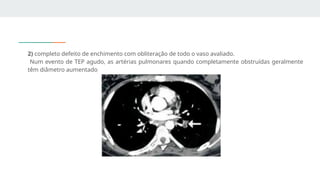

2) completo defeito de enchimento com obliteração de todo o vaso avaliado.

Num evento de TEP agudo, as artérias pulmonares quando completamente obstruídas geralmente

têm diâmetro aumentado

2) completo defeitode enchimento com obliteração de todo o vaso avaliado. Num evento de TEP agudo, as artérias pulmonares quando completamente obstruídas geralmente têm diâmetro aumentado